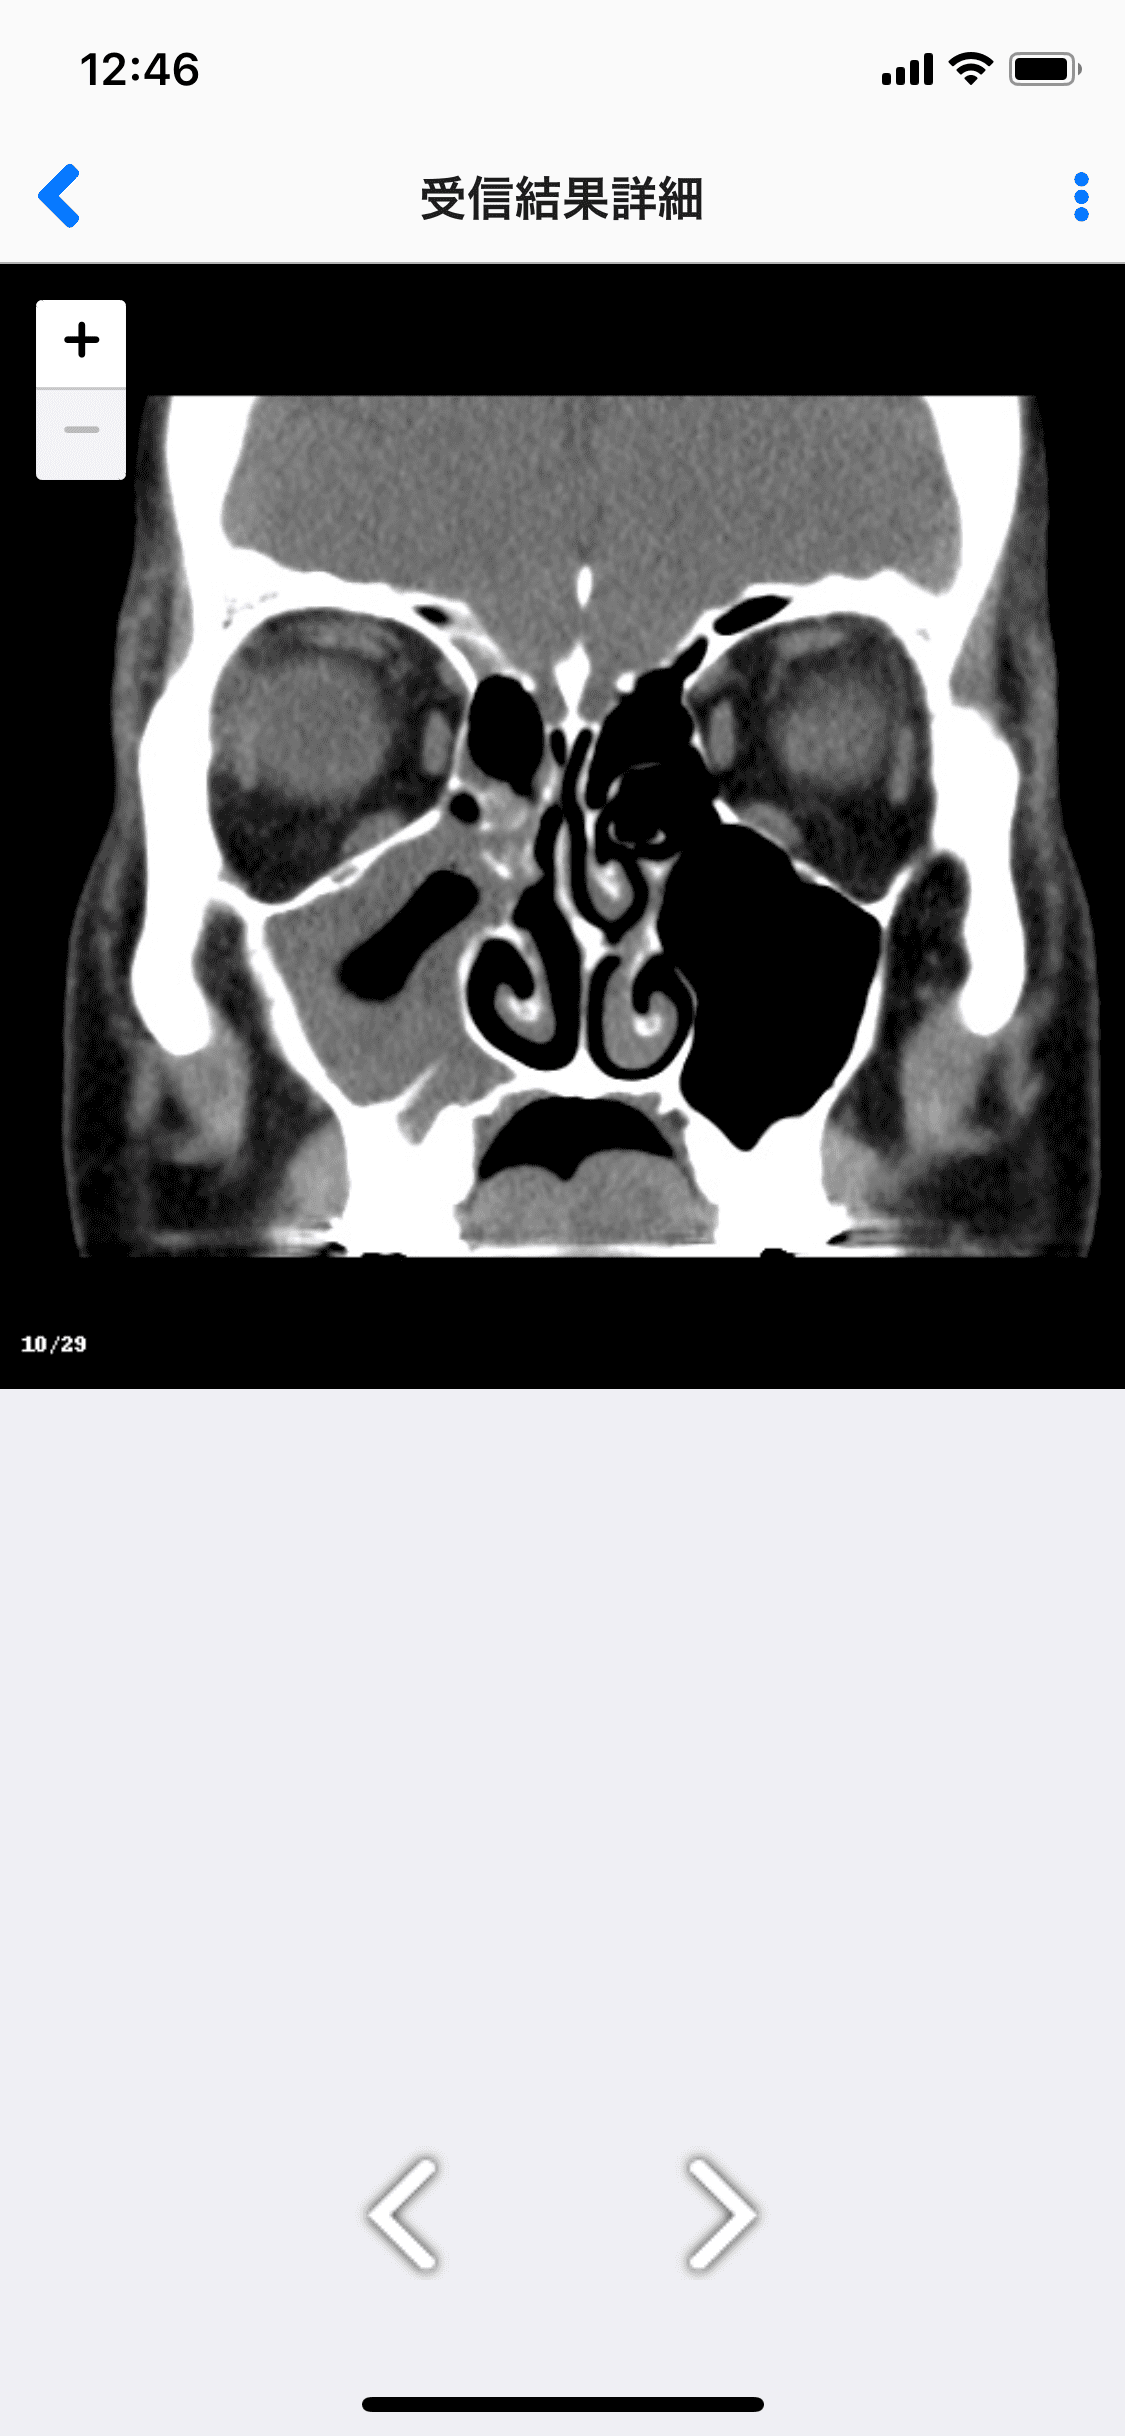

■受信結果詳細画面

※画像はサンプルです。